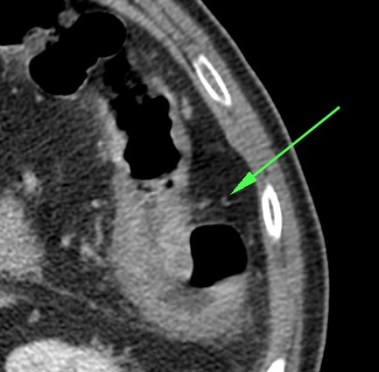

Se realiza TC de abdomen en vacío y con contraste en fase portal:

Estamos ante un cuadro de isquemia intestinal en un paciente con bajo gasto cardiaco con afectación principal de asas intestino delgado, territorio vacularizado por la arteria mesentérica superior.

Flecha roja: colateral que repermeabiliza la AMS.

La presencia de neumatosis portal y mesentérica consiste en pequeñas burbujas de gas dentro de los vasos mesentéricos o que también pueden extenderse hacia las ramas intrahepáticas de la vena porta, encontrándose típicamente en la periferia del hígado.